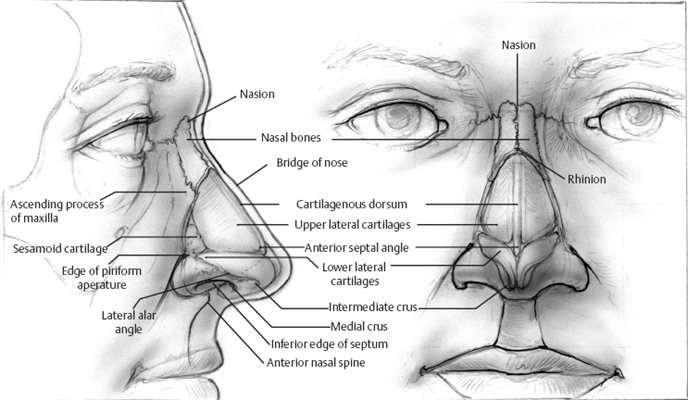

鼻中隔偏曲圖片

鼻中隔彎曲手術圖解 (5)

鼻中隔彎曲手術圖解 (6)